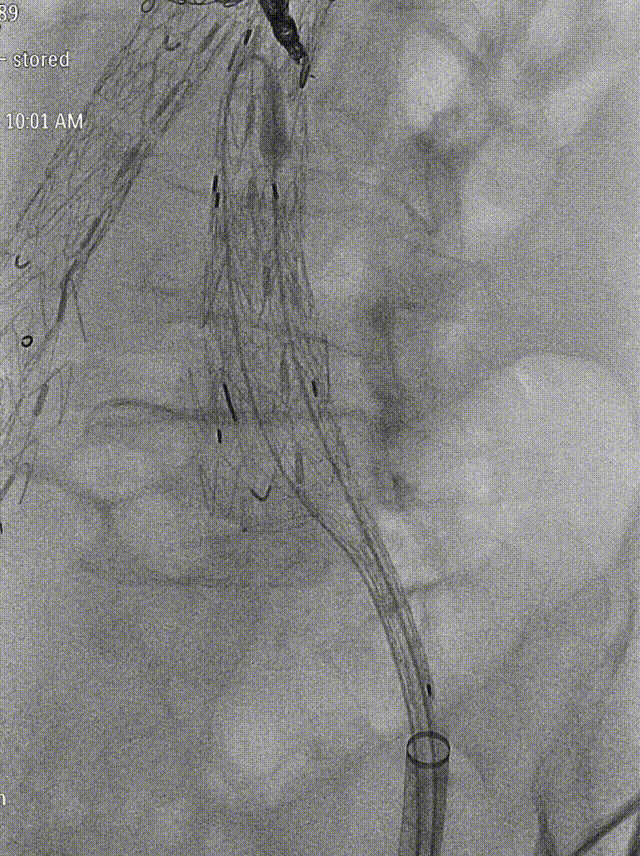

导丝配合导管沿DSF1245鞘选至髂内远端,交换Amplatz导丝,植入GORE髂内分支支架HGB161207(16mm-12mm-70mm),退鞘,手推造影确认位置后释放。髂外动脉起始段及髂内动脉中段见受压。导入球囊(8mm*40mm)扩张髂内动脉狭窄处,并予以CODA球囊扩张髂外动脉起始段狭窄处。

gore医疗怎么样「漫腹精论」独具匠心 推陈出新——同侧IBE支架内翻山重建髂内动脉治疗EVAR术后内漏病例报道_https://www.jmylbn.com_新闻资讯_第18张

植入髂内分支

gore医疗怎么样「漫腹精论」独具匠心 推陈出新——同侧IBE支架内翻山重建髂内动脉治疗EVAR术后内漏病例报道_https://www.jmylbn.com_新闻资讯_第19张

释放髂内分支

gore医疗怎么样「漫腹精论」独具匠心 推陈出新——同侧IBE支架内翻山重建髂内动脉治疗EVAR术后内漏病例报道_https://www.jmylbn.com_新闻资讯_第20张

球囊扩张

造影:支架定位准确,形态良好,未见明显受压。双侧肾动脉显影同前,原主动脉及双侧髂动脉血流通畅,至延迟相瘤腔内未见明显内漏,左侧髂内动脉显影可。